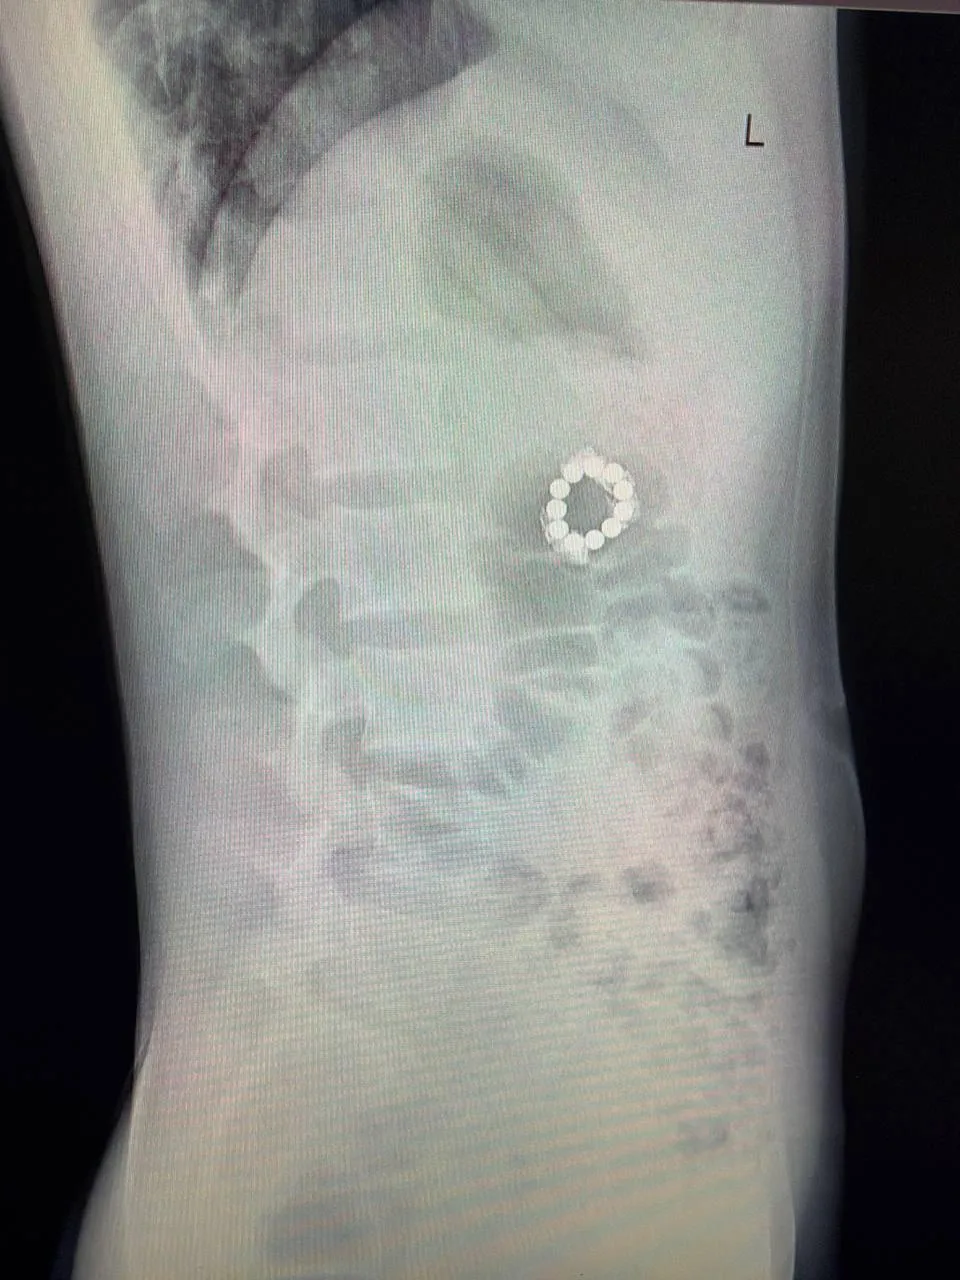

Инородные тела обнаружили, когда мальчику сделали томографию из-за боли в спине после неудачной тренировки по самбо.

Снимок не показал повреждений позвоночника, однако в желудочно-кишечном тракте пациента выявили магниты. Ребенок признался, что проглотил их из любопытства. Через некоторое время у него появились боли в животе и рвота.

«Мы обнаружили семь магнитов в проекции желудка и еще четыре — в других отделах желудочно-кишечного тракта. За долгие годы они сцепились друг с другом, что привело к перфорации стенки желудка. Это жизнеугрожающее состояние при котором нарушается кровоснабжение и образуются сквозные отверстия», — пояснил заведующий отделением эндоскопических методов диагностики и лечения Александр Иноземцев.

Во время срочной операции из желудка мальчика извлекли семь магнитов малоинвазивным методом. Еще четыре продвинулись глубже по пищеварительному тракту, поэтому хирургам пришлось выполнить полостную операцию.